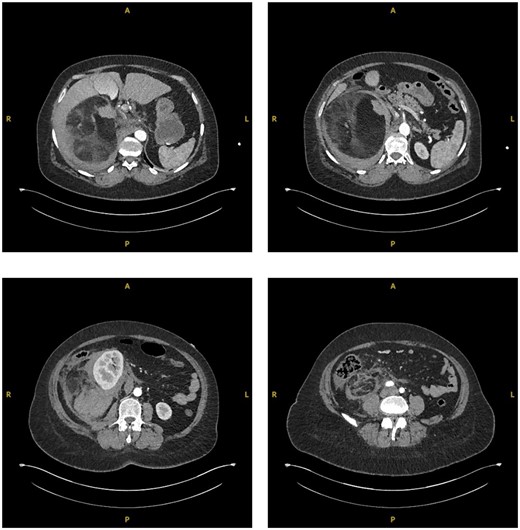

On interval CT scanning, the adrenal lesion was shown to have decreased in size (14.3×13.2 cm), likely due to reduction of intralesional haematoma, and no active haemorrhage identified (Fig. 3). There was an incidental finding of filling defects in the right lower lobe pulmonary artery. The patient was therefore re-admitted to work-up for PE. The patient was asymptomatic of venous thromboembolism. A CTPA identified bilateral segmental and sub-segmental pulmonary vessel filling defects, with no evidence of right heart strain. This therefore warranted commencement of anticoagulation; however, the patient remained at risk of re-haemorrhage of the adrenal lesion. On discussion with different relevant specialties and after counselling the patient on the risks and benefits, it was decided to commence on treatment dose Enoxaparin (low-molecular weight heparin). Due to her higher propensity of haemorrhage, the patient remained as an inpatient for close observation of signs of haemodynamic compromise. The patient remained well on Enoxaparin and was eventually discharged.

Interval CT imaging showing decrease in size of lesion and surrounding haematoma.